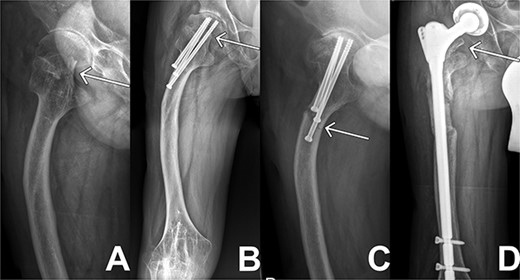

Initially, the patient presented to our joint consultation with a femur head necrosis ARCO 4, a femur deformity and arthritic hip changes, thus we initialized an elective total endoprosthesis (TEP) of the right hip. Before the operation, the patient was represented to our emergency department after a falling on the right hip with inner rotation pain. A medial femoral neck fracture of Garden 4 as seen in Fig. 1(A) was diagnosed. Because of his young age and the presented situation, we decided to perform a joint-presenting closed reduction and internal triple screw fixation of the proximal femur using 3 × 6.5 mm titanium cannulated screws the following day.

X-ray sequences of the right hip in different resolutions. (A) Representation of the medial femoral neck fracture before the first intervention as highlighted by arrow. (B) Osteosynthesis intervention of hip is highlighted by arrow few months after intervention. In addition, femoral deformity and knee rigidity are recognizable. (C) Periosteosynthetic fracture of the femoral shaft shortly before intervention. (D) Follow-up image of the inserted prosthesis material shows regular position.